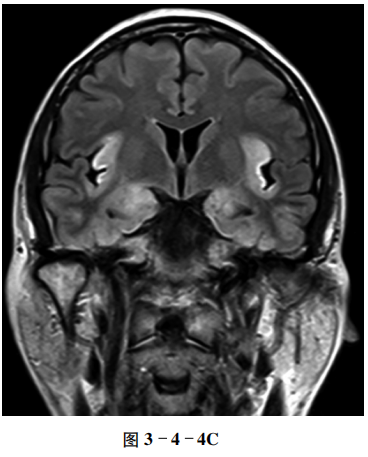

例4 病毒性脑炎

【病史摘要】 男性,46岁。发热9天,意识不清伴频繁抽搐3天。

【CT及MRI征象】 CT平扫示双侧颞叶、岛叶片状稍低密度影,边界模糊,局部脑沟变窄(图3-4-4A、B)。MRI T2-FLAIR(液体衰减反转恢复序列)显示双侧病变位于颞叶海马及岛叶,并较对称分布(图3-4-4C)。

【重要征象】 双侧边缘叶稍低密度影,刀切征(与豆状核分界清晰)。